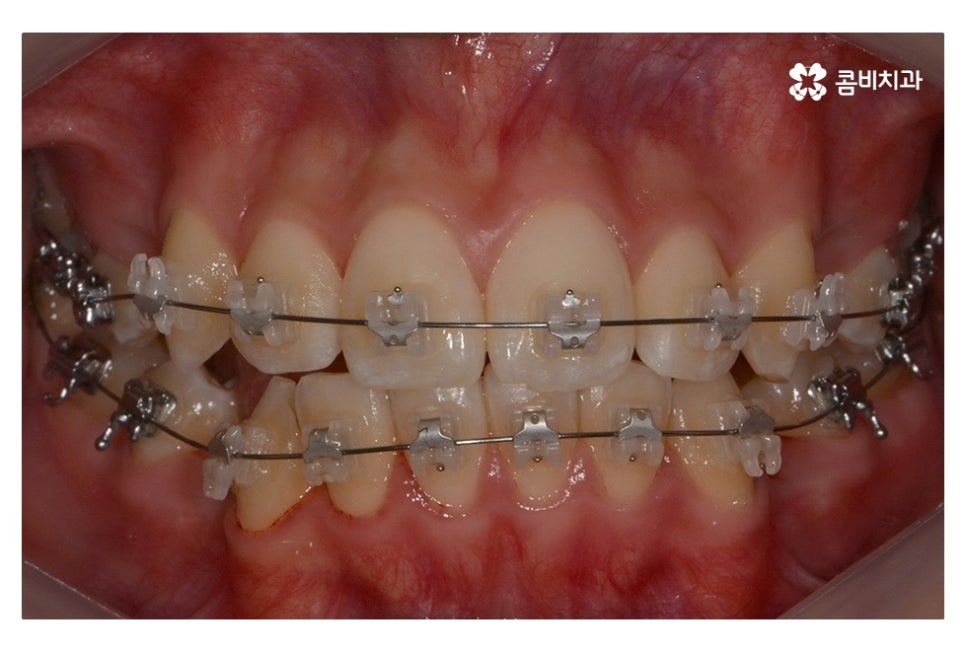

위 사진에서 보시면 시간이 지나면서 발치를 했던 치아의

공간이 사라지고 교정을 통해서 치열이 가지런해진 것을 확인할 수 있는데요.

중학생치아교정에 있어서 중요한 사항이 단지 치열만이

가지런해 보이는 것이 아닌 얼굴과의 조화와 교합이라 할 수 있어요.